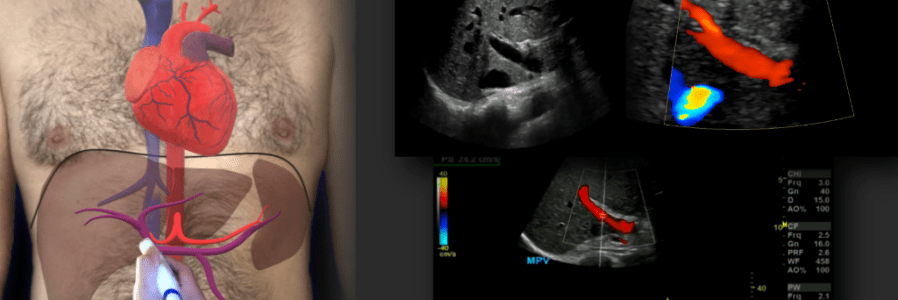

Portal Vein Doppler

Anatomy The Portal Vein is made up three main vessels the Superior and Inferior Mesenteric veins and the Splenic vein. When these three vessels converge they become the Main Portal Vein which enters the Liver via the porta hepatis along with the hepatic artery and common bile duct (cbd exits the liver), aka the Portal… Read More Portal Vein Doppler